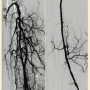

Peripheral angiography showed total occlusion of the right distal superficial femoral artery extending into the popliteal artery and into the trifurcation, with reconstitution of a peroneal and a posterior tibial. We attempted to obtain antegrade access to the lesions of the right infra-popliteal vessels (Figure 1). After failing to cross the lesion, we obtained retrograde access, puncturing from below the lesion through the posterior tibial artery near the ankle joint (Figure 2). Access was obtained and the lesion below the knee was crossed (Figure 3). Following this, the V-18 control wire (Boston Scientific) was snared from above, a CXI support catheter (CSI) was backloaded over the wire, and an antegrade Viperwire (CSI) was then placed, with removal of the retrograde sheath and wire. Atherectomy was performed with the 1.5mm Stealth 360° orbital atherectomy device (CSI) followed by balloon angioplasty with Cook, Sterling (Boston Scientific), and Chocolate (Cordis) balloon catheters. After angioplasty, significant improvement in luminal gain was noted at the expense of a dissection (Figure 4). We chose to place a Zilver PTX drug-eluting stent (Cook) within the distal superficial femoral and popliteal artery segment (Figure 5). After the procedure, the patient’s wounds completely healed. An angiogram 3 months later was performed, showing the vessels to be widely patent (Figure 6). The patient sent us a video of himself finally walking, and without pain (Video 1; online).